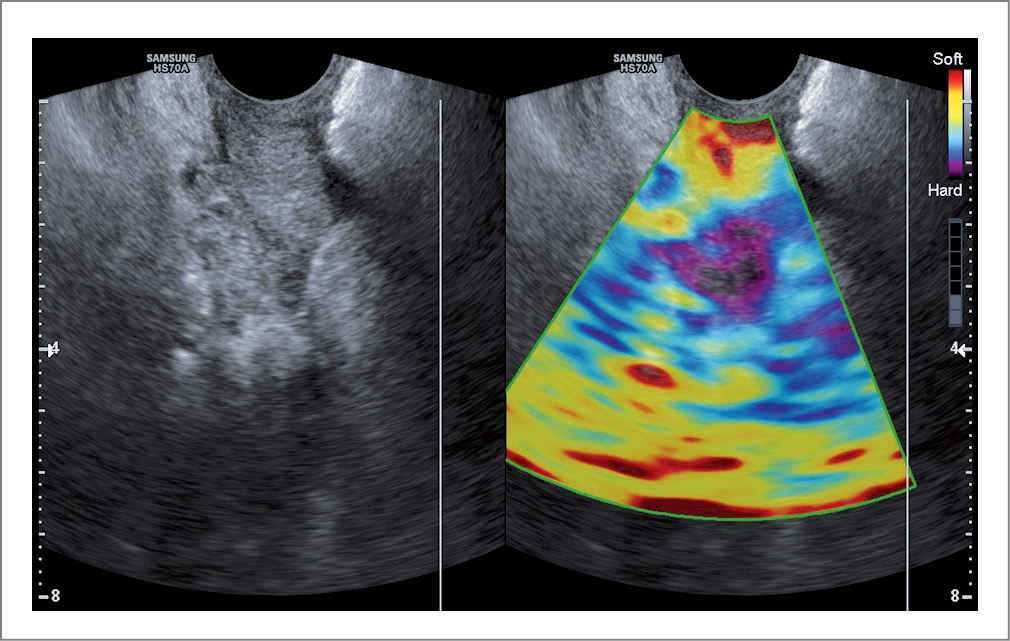

При проведении ультразвукового исследования с эластографией после операции и проводимой терапии в 1 и 2-й группах преимущественно отмечалось повышение эластичности тканей влагалища. На эластограмме ткани стенок влагалища картировались зеленым цветом с участками синего (рис. 3). Коэффициент деформации увеличился относительно показателей до операции. Через 3 мес после операции в 3-й группе по-прежнему преобладала средняя и низкая степени эластичности тканей стенок влагалища и более низкие показатели коэффициента деформации относительно 1 и 2-й групп (рис. 4).

Рис. 3. Ультразвуковое исследование с эластографией после операции. / Fig. 3. Postoperative ultrasound with elastography.